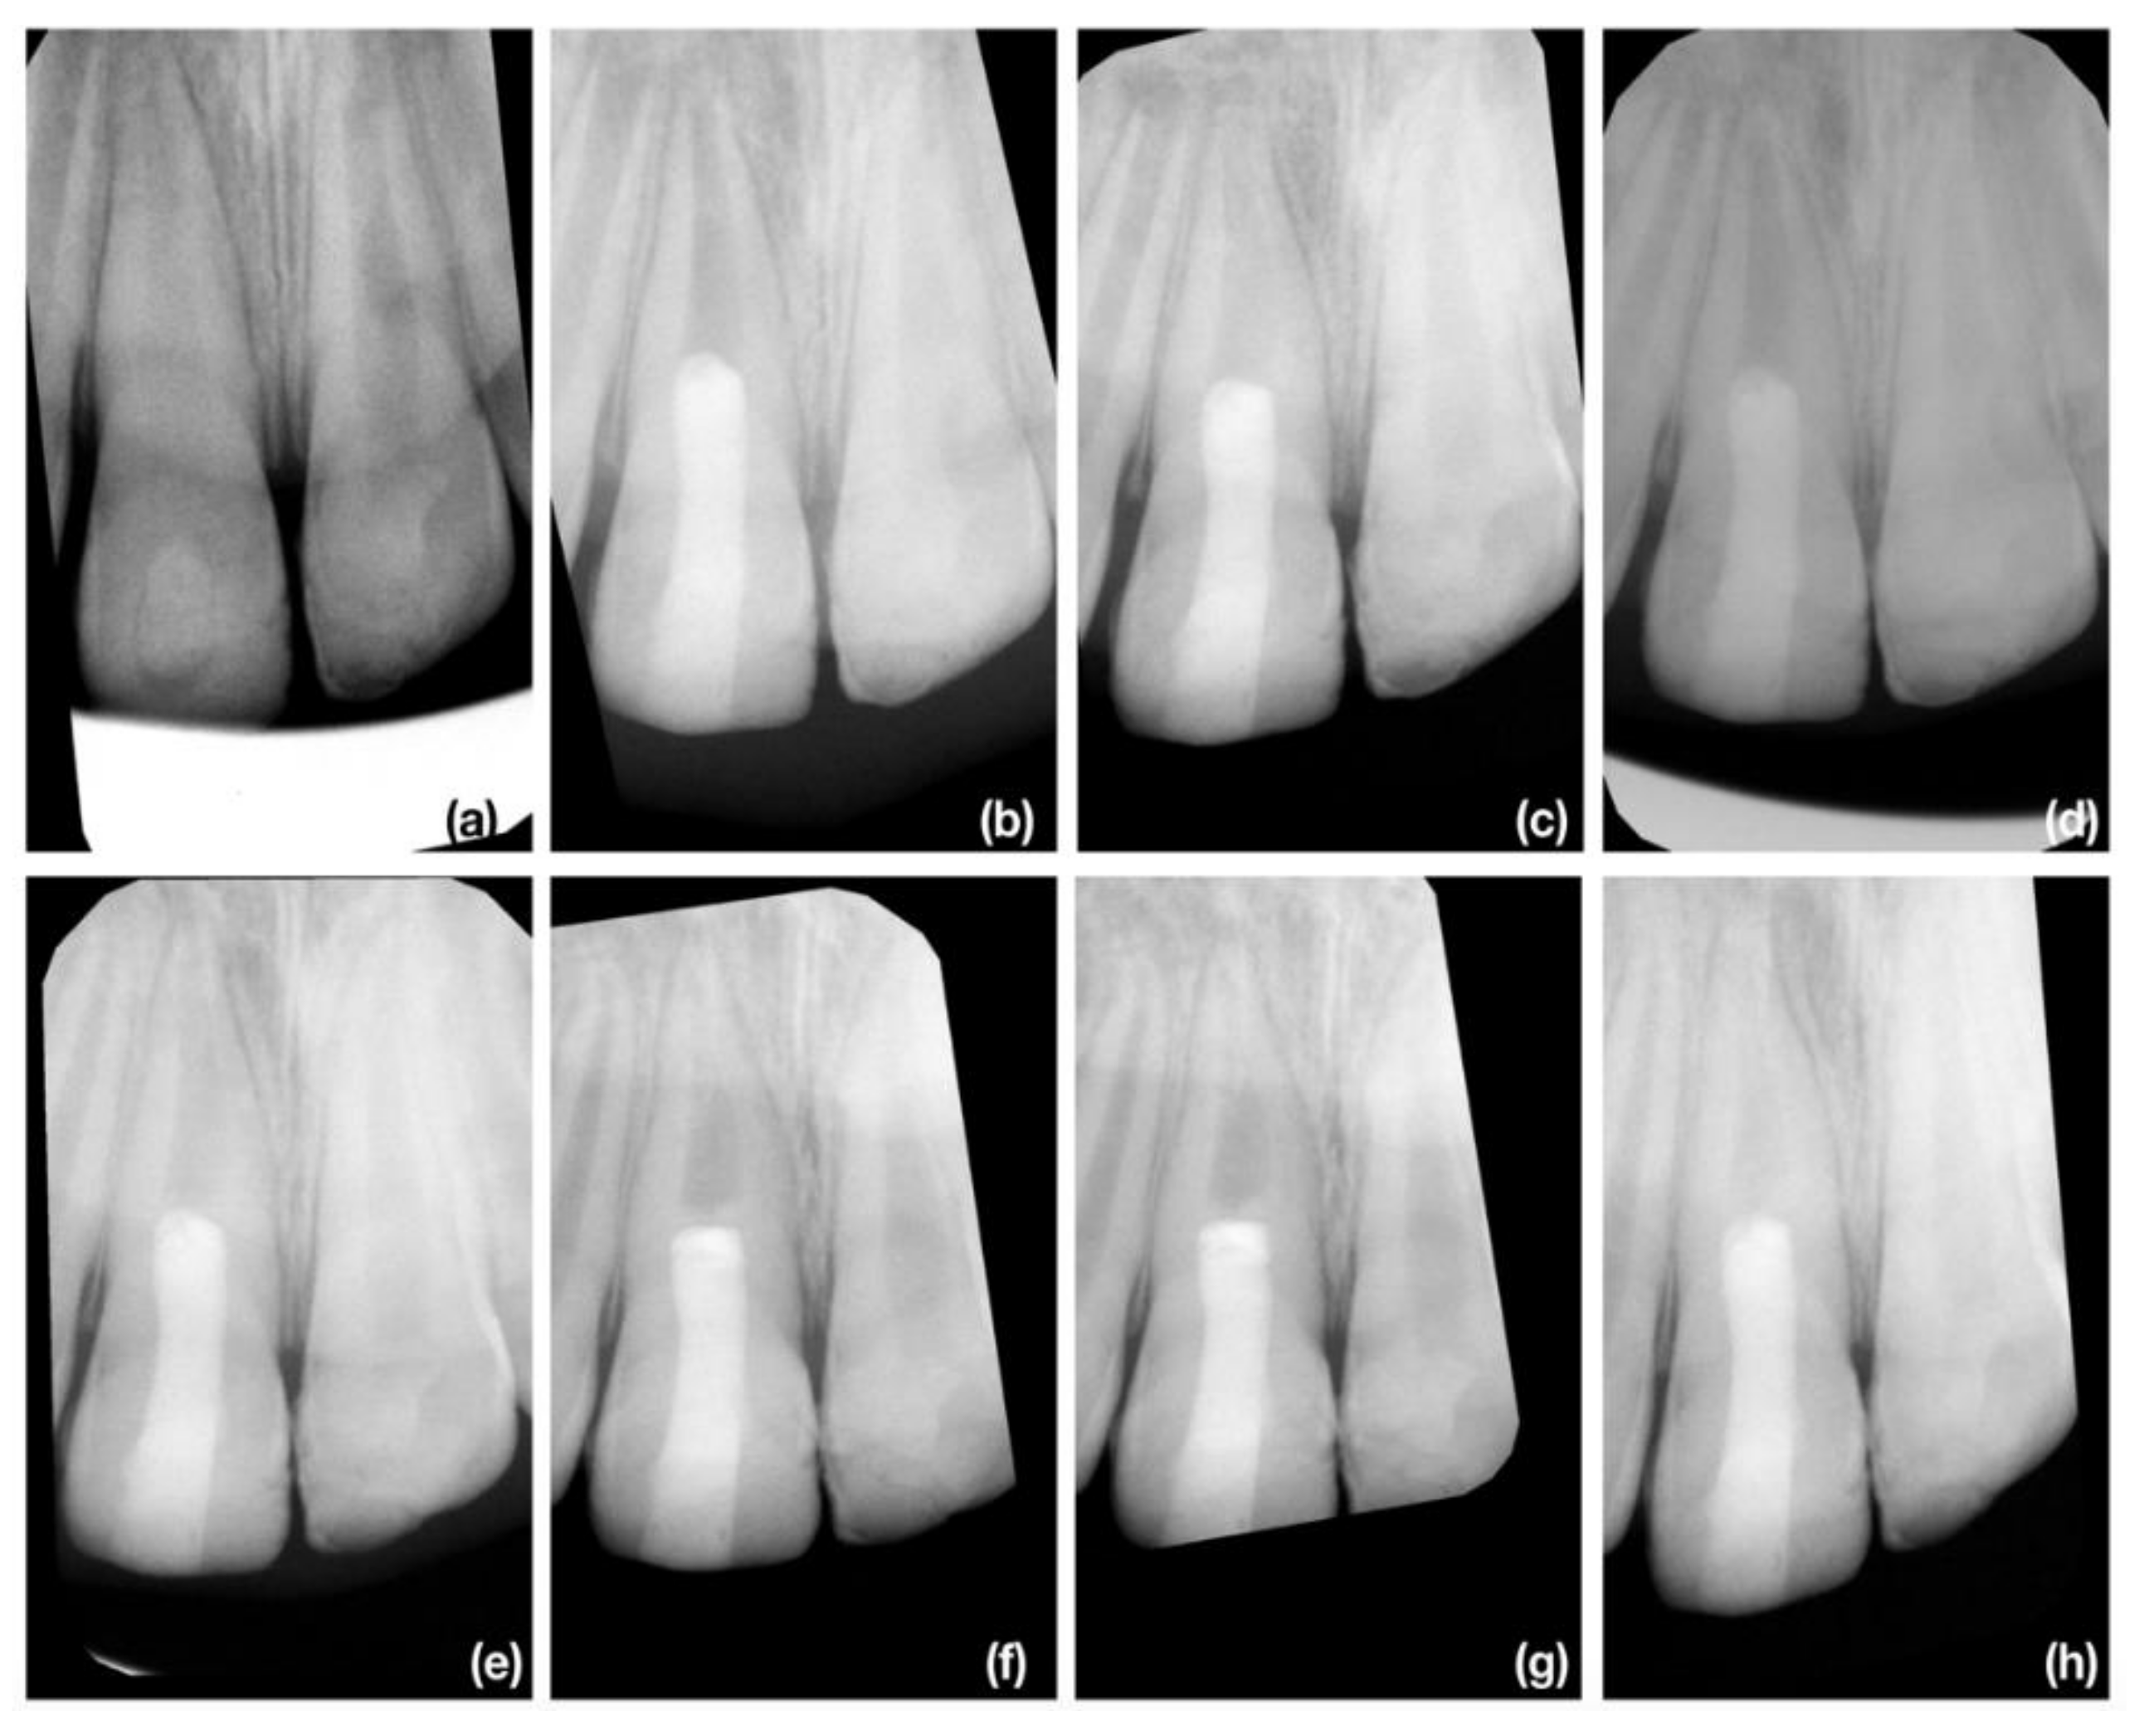

3.2. Radiographic Root Length Change

3.3. Radiographic Root Width Change

3.4. Radiographic Root Area Change